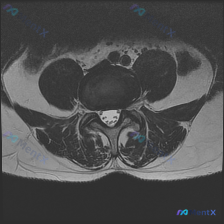

这是一张腰椎MRI T1加权轴位图像,对应腰椎下段(L4/5或L5/S1椎间盘水平),影像所见如下:

- 骨性结构:椎体后缘轮廓清晰,椎弓根、椎板及关节突关节结构未见异常;椎体骨髓信号均匀,无局灶性异常信号

- 椎间盘:椎间盘后缘轮廓平滑,未见局限性后突或膨出征象,和硬膜囊前缘界限清晰

- 椎管与神经:椎管无明显骨性狭窄,两侧侧隐窝形态正常,有硬膜外脂肪填充,无明确闭塞受压;黄韧带无增厚内突;硬膜囊形态基本正常,马尾神经信号未见异常

- 软组织:椎旁肌肉信号均匀,无异常肿块或信号异常

- 无红旗征象:未见骨质破坏、椎管内占位等严重病变表现